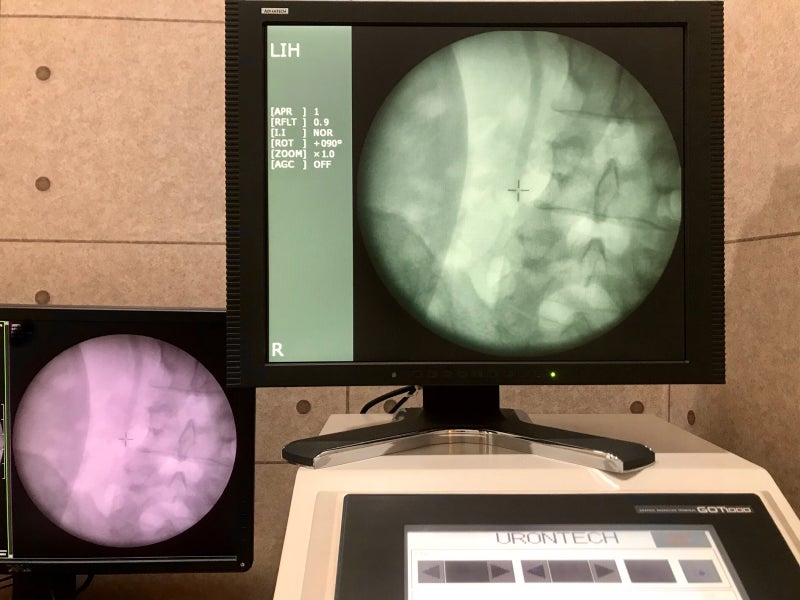

의정부상행비뇨기과에서는 남성환자에게 효율적인 진료를 할 수 있는 능력과 전문성을 갖추고 있으며, 대학병원 수준의 정밀장비를 갖추고 있어 세밀한 검사와 진료, 수술이 가능한 의료서비스를 제공하고 있습니다.참조하십시오